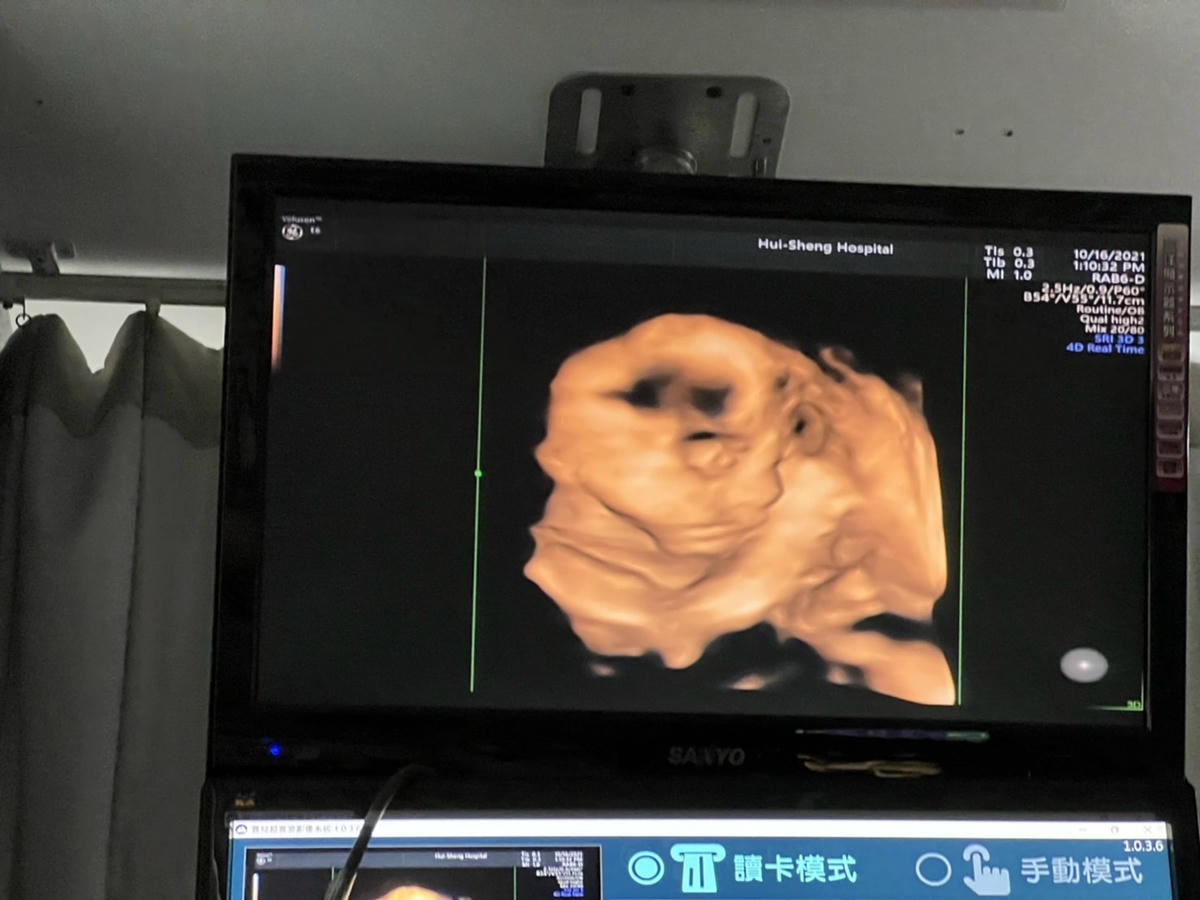

看完寶寶的發展大小就要進入我最最最期待的部分,蕙生醫院最新引進 3D/4D超音波

不用在看黑黑的超音波螢幕,來到這邊寶寶的一舉一動看的超!清!楚!

寶寶今天算給我一點點面子能看見側面的部份,因為寶寶的臉卡在我的胎盤下面,

所以要完完全全看見整張臉有點困難,院長人也超好一直努力幫我盡可能看見寶寶的樣子

這次來到蕙生醫院產檢,醫院在九月份引進了新儀器,可以讓孕媽媽們看到超清楚的寶寶

院長說3D/4D超音波的範圍只有在下面框框裡,如果寶寶貼著胎盤角度也就會不好看見

也有拿到寶寶的超音波照片,照的好清楚喔 比我自己看的婦產科還清楚超多

最近產檢完全不知道照片在拍什麼… 謝謝蕙生醫院讓我看到超清楚的寶寶照可以留念